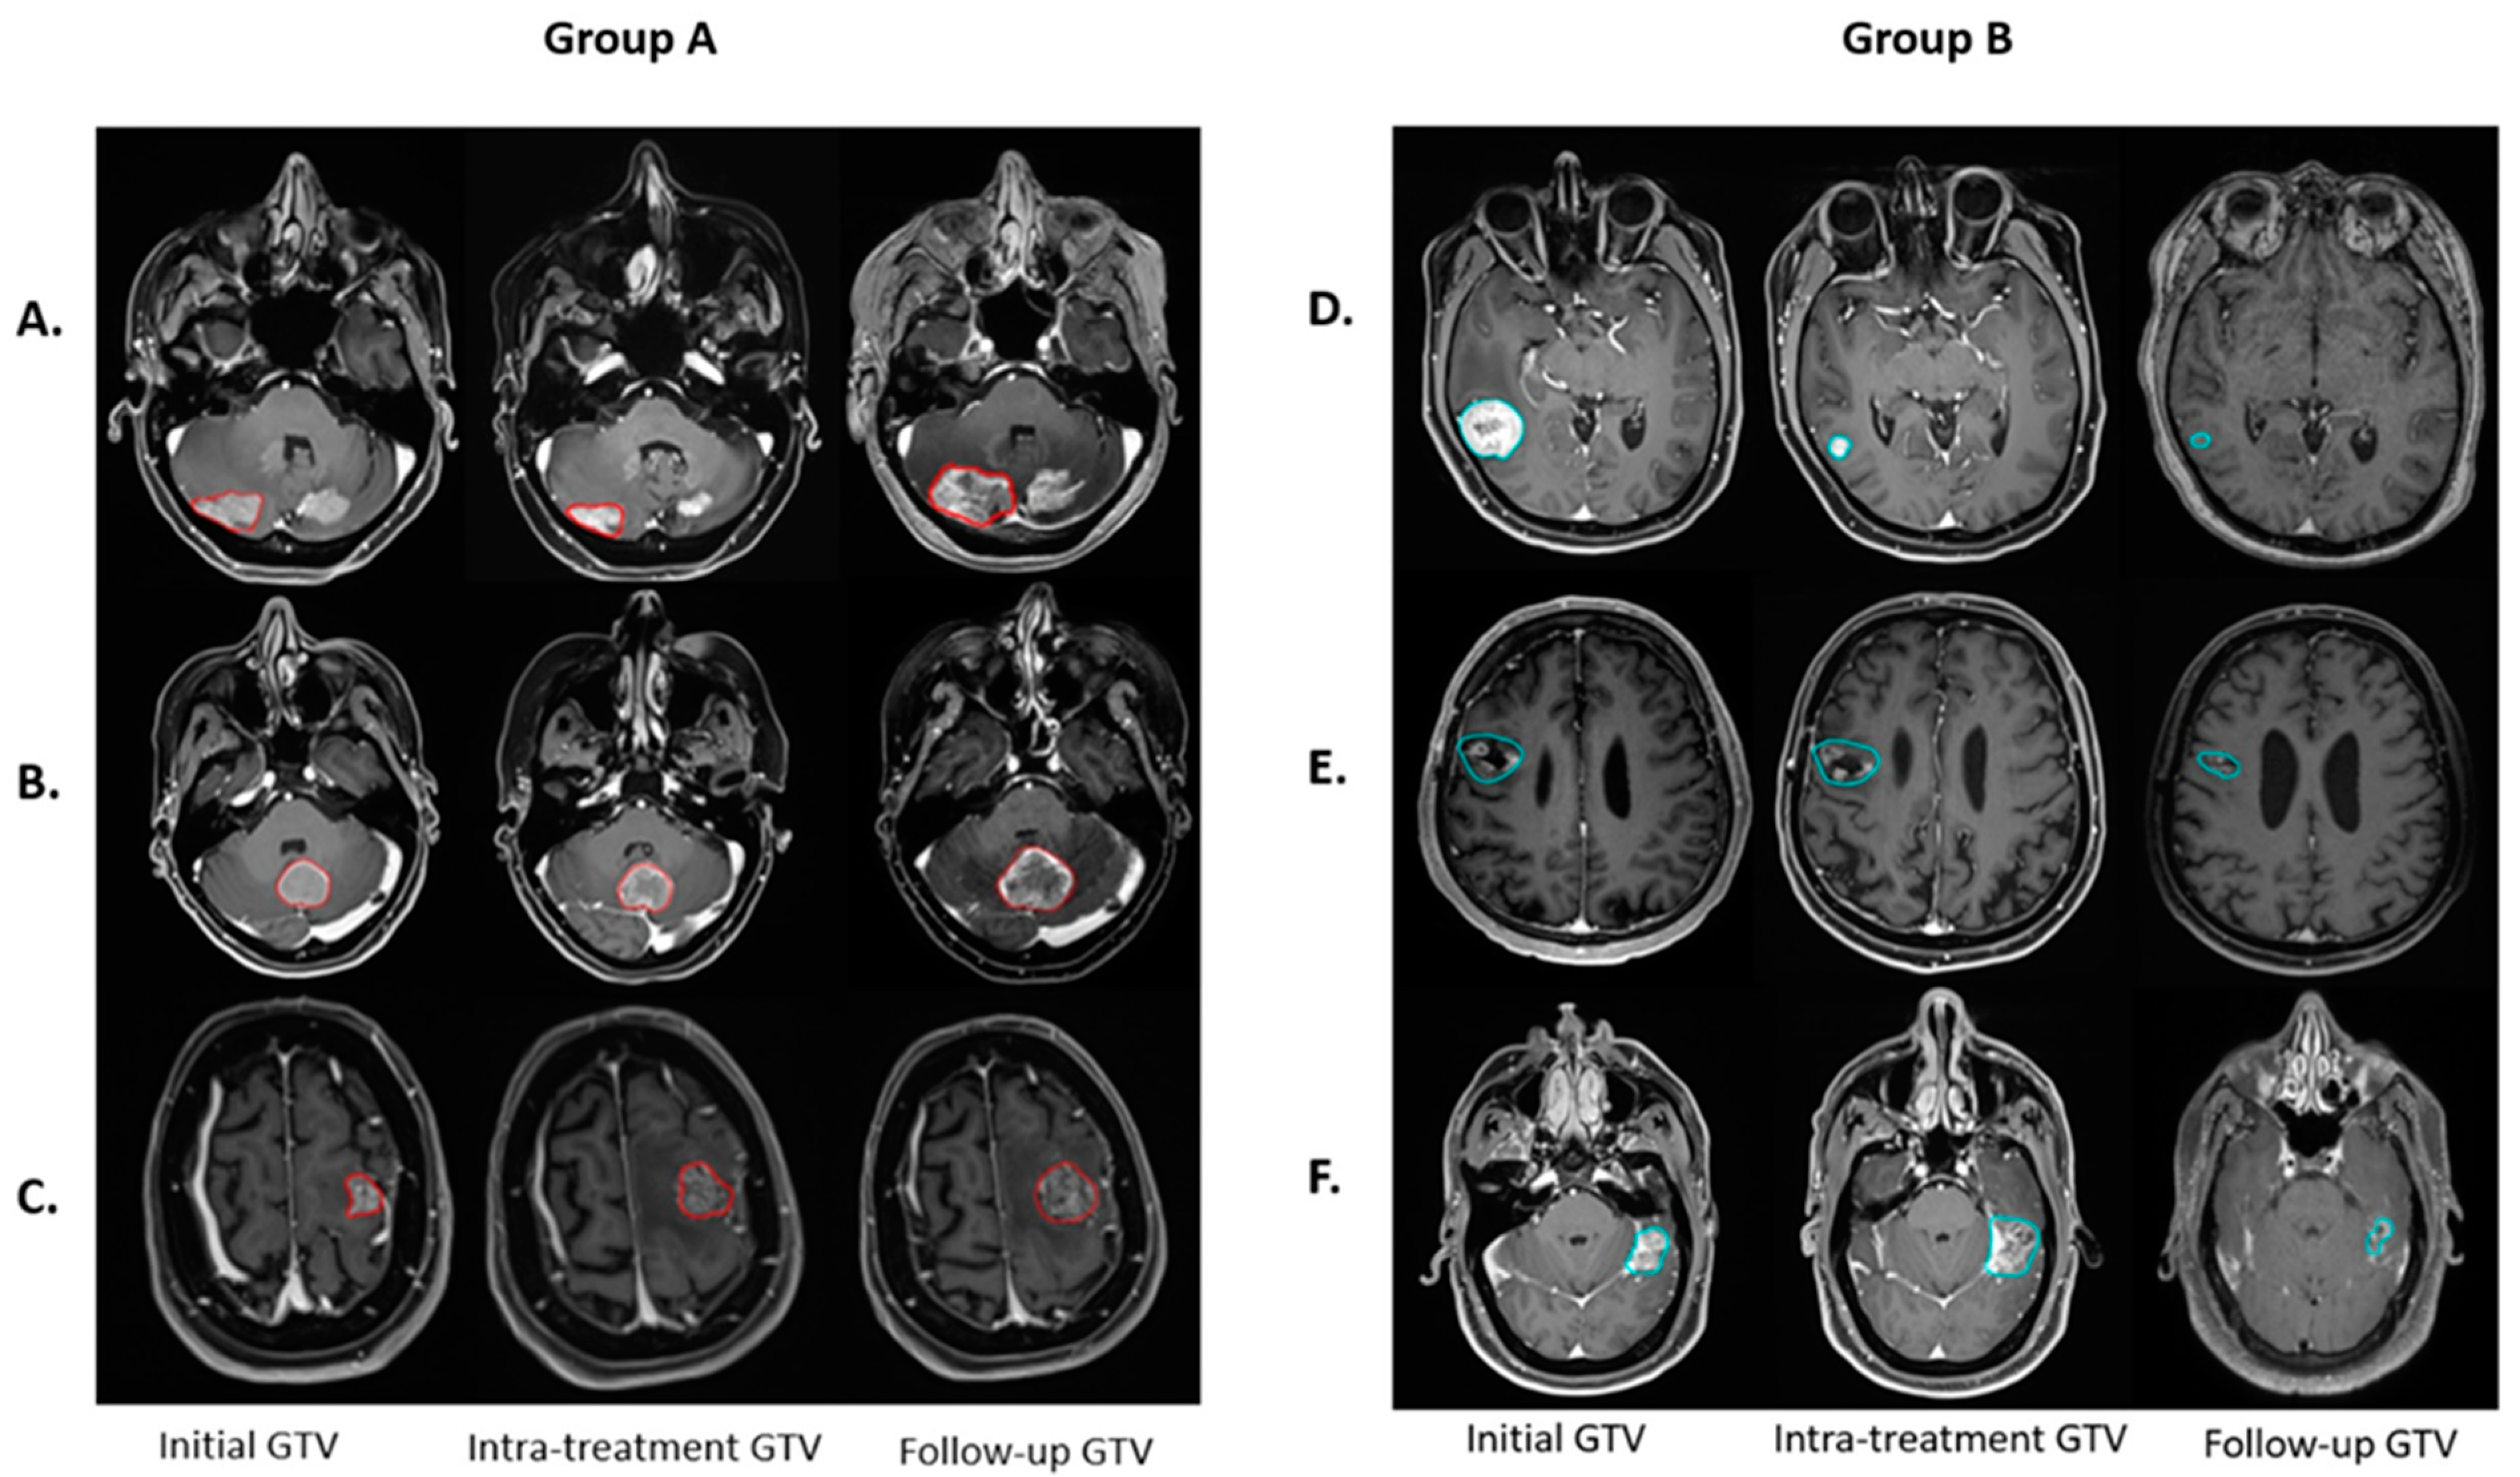

3.1. Treatment Response